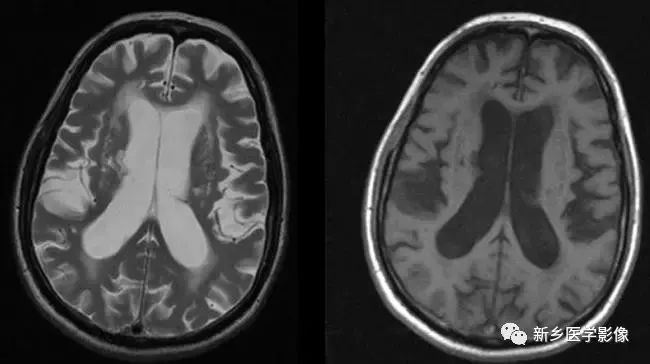

8.胼胝体发育不良

在脑发育腹侧诱导晚期,新形成的端脑嘴侧壁的背侧部分增厚、内陷,向后沿尚未完全发育的大脑半球间裂延伸。两个月后形成一个连合即胼胝体纤维的细胞框架,该细胞框架形成后胼胝体相应部分立即发育。膝部先发育。然后是体部、压部.位于胼胝体膝部后下方的胼胝体嘴最后发育。如果胼胝体发育过程中出现有害因素,就有可能导致胼胝体发育不良.表现为完全缺如或部分缺失。常表现为膝部存在或膝部和体部存在。压部和胼胝体嘴缺失。

胼胝体发育不良可见单独发病,但更常见的是伴有中枢伸经系统的其他畸形,包括胼胝体周围脂肪瘤、脑膨出、交通性脑积水Chaiarii畸形、Dandy-Walker囊肿、脑裂畸形等。临床上可无症状或仅有轻度临床症状,临床检查可见眼距过宽、大头畸形、智力发育迟滞等。胼胝体缺失时,MR冠状位上侧脑室前角呈新月形表现,侧脑室体部分离,呈垂直状平行走行。